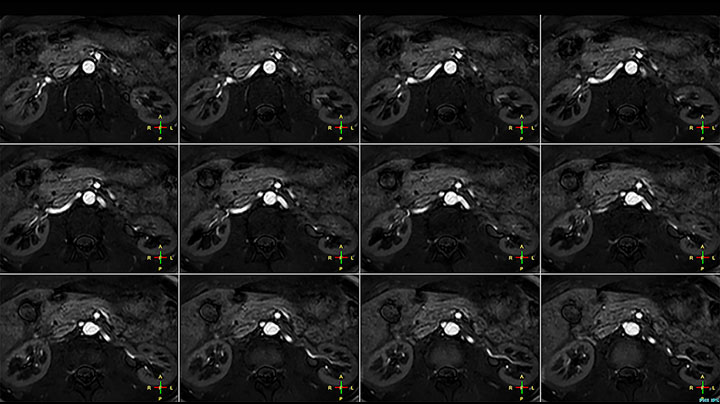

Whole body diffusion

A 61-year-old female with a malignant lymphoma underwent an MRI exam with whole body diffusion weighted imaging (DWIBS) as well as PET. On the images shown, the resolution of DWIBS is better than PET, which allows visualization of the small pelvic lesions and almost no distortion is seen in the neck area.

Prodiva MRI whole body DWI lymphoma, Seirei Mikatahara

Prodiva MRI whole body FDG-PET, Seirei Mikatahara